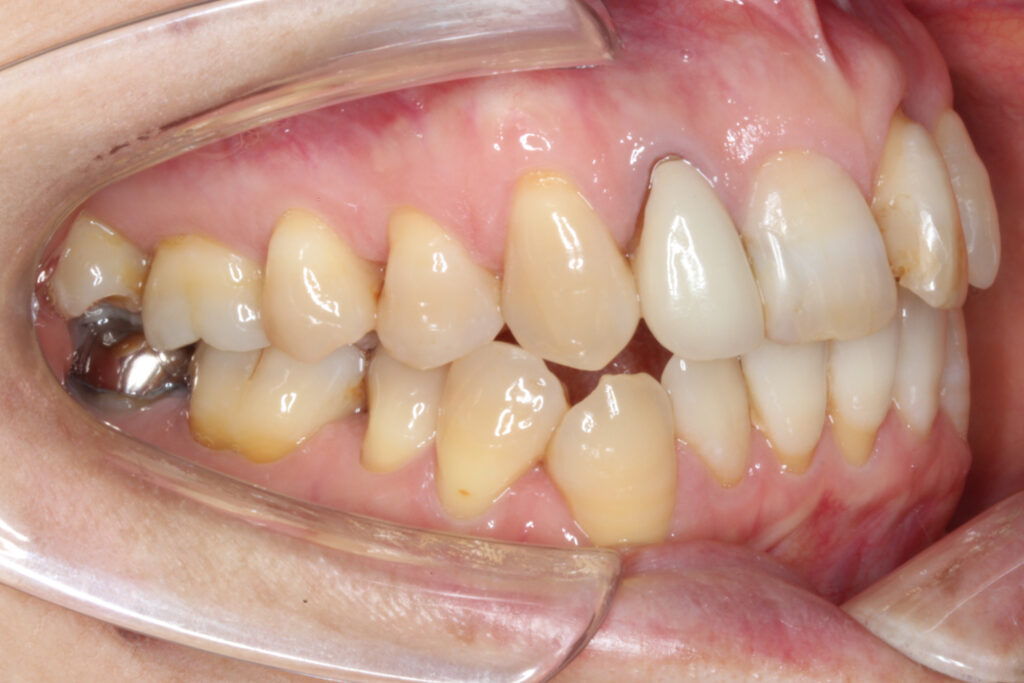

右上の2番目の前歯が完全に内側へ転位しており、1番目の前歯は大きく捻じれている状態です。

それに伴って上顎の歯並びの中心が左側へずれてしまっています。

また、下顎の前歯にもがたつきがあり、左下奥歯はブリッジが入っている状態です。

ブリッジがあると歯が繋がってしまっているため移動させることが困難になりますが、今回はブリッジを壊さずになんとか治療を進めることとしました。

Before